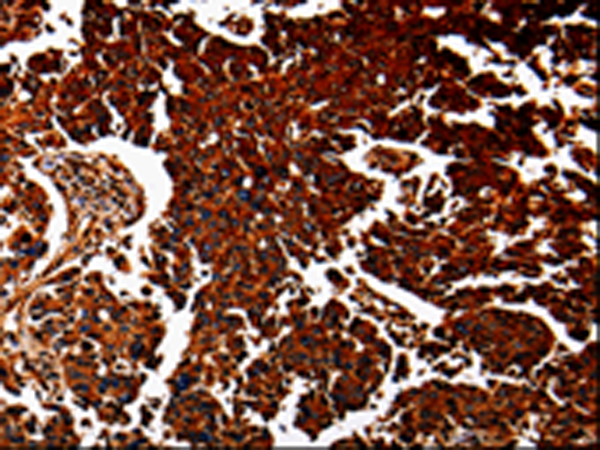

IHC positive control: |

Human lung cancer and human renal cancer |